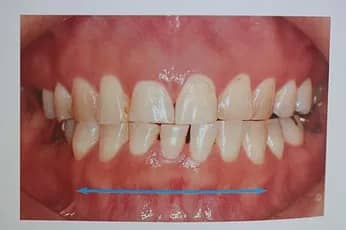

術前術後BEFORE AFTER

AFTER

歯がすり減ることによって、歯の長さが短くなっています。